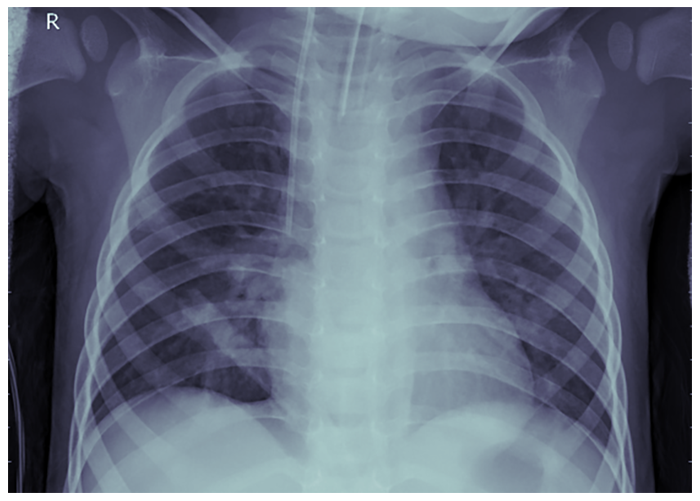

Fig. 5. Radiografie pulmonară - Pneumonie - PAUL MOONEY, 2018 (Chest X-Ray Images (Pneumonia) | Kaggle )

Acesta este locul unde Machine Learning poate fi de ajutor, prin automatizarea procedurii de diagnosticare, care necesită mult timp. În acest exemplu, am folosit librăria TensorFlow împreună cu un model pe TensorHub și setul de date de radiografii toracice de la Kaggle (Fig. 4 este a unui pacient sănătos, iar Fig. 5 este a unui pacient cu pneumonie). Pentru ochiul neexperimentat și chiar pentru cel al unui medic experimentat, acestea ar părea poate greu de distins, ceea ce este de înțeles. Să ne amintim că un medic dedică cea mai mare parte a timpului diagnosticării pacientului și dacă încercăm să distingem cele două scanări putem înțelege de ce.